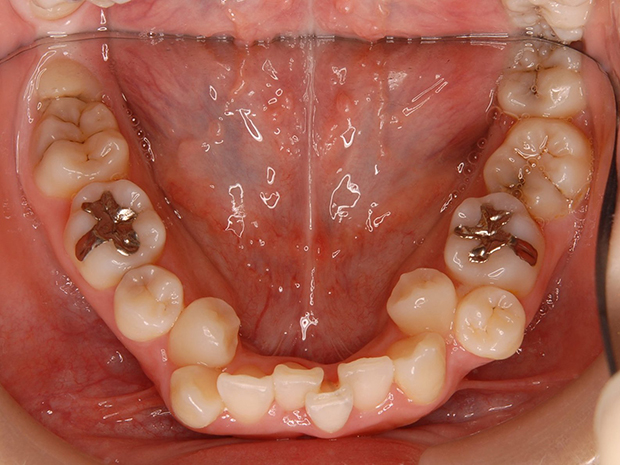

【埋伏歯】下顎前突 小児矯正 表側マルチブラケット装置

| 主訴 |

上の歯が出てこない 受け口 |

||

|---|---|---|---|

| 診断名 |

上顎左側中切歯、側切歯の埋伏歯および側切歯、犬歯の移転歯を伴う反対咬合 |

||

| 年齢 | 8歳 | 性別 | 女子 |

| 治療に用 いた装置 |

舌側弧線装置 唇側マルチブラケット装置 (メタルワイヤー) | 抜歯部位 | 非抜歯 |

| 治療期間 ・回数 |

3年10か月・46回 | 治療費 概算 |

約40万円 (調整料を含む) |

| 治療内容 詳細 |

前歯が生えてこないのをかかりつけの歯科医院にて指摘され、ご紹介された患者様です。虫歯も多い子でしたが、虫歯の治療、管理も同時に行い、小児矯正だけで綺麗に治りました。 |

||

| リスク・ 副作用 |

装置による違和感 疼痛 虫歯のリスクなど |

||